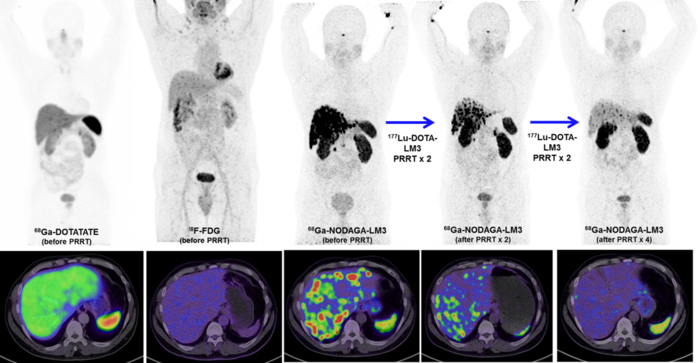

Reston, VA— A new type of peptide receptor radionuclide therapy (PRRT) has been shown to control disease in 85 percent of patients with metastatic neuroendocrine neoplasms, achieving complete remission in some patients. The first-in-human study utilized 177 Lu-DOTA-LM3 therapy, which was administered without severe adverse effects and was well tolerated by the majority of patients. This research was published in the November issue of The Journal of Nuclear Medicine .

To further investigate the role antagonists can play in treating neuroendocrine tumors researchers developed a study to determine the safety, biodistribution and efficiency of a new type of SSTR antagonist, 177 Lu-DOTA-LM3. Fifty-one patients with progressive, heavily pretreated neuroendocrine neoplasms underwent PRRT with 177 Lu-DOTA-LM3. Treatment-related adverse events were graded for all participants, and dosimetry was performed for 11 patients.

177 Lu-DOTA-LM3 was administered without severe adverse effects and was well tolerated by most patients. Disease control was reached in 40 out of 47 patients (85 percent) who were monitored after 177 Lu-DOTA-LM3 therapy. Two patients achieved complete remission by the European Organization for Research and Treatment of Cancer criteria.

Of note, the uptake and dosimetry of the antagonist 177 Lu-DOTA-LM3 were compared with those of the commonly used SSTR agonist 177 Lu-DOTATOC in patients undergoing treatment on the same dosimetry protocol. 177 Lu-DOTA-LM3 demonstrated higher uptake and a longer effective half-life in tumor lesions, resulting in higher tumor radiation doses than for agonist 177 Lu-DOTATOC.